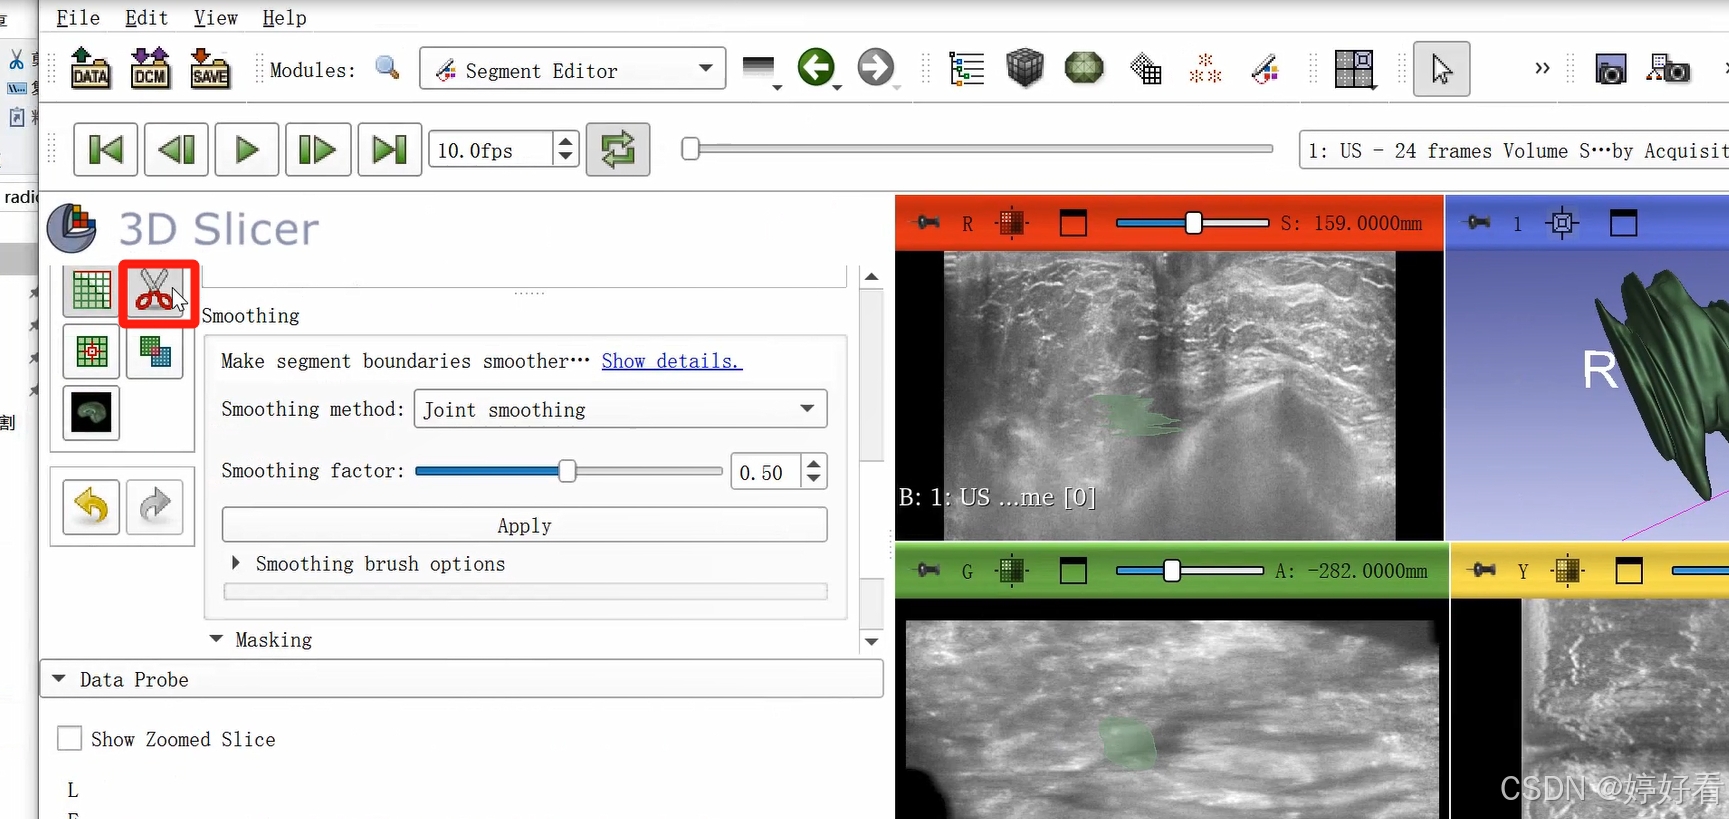

2.7 Smoothing功能使图像表面更光滑

首先,选中Smoothing功能,然后选择Joint smoothing,最后点击Apply。